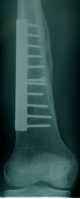

X-ray

Solitary, eccentric lytic lesion

Non-Ossifying Fibroma (NOF)

- > 2 cm

- eccentric metaphyseal lesion

- sclerotic margin

- slight expansion of cortex

- usually < 1/3 diameter of bone

2. Operative management

- failure to obtain or maintain an adequate reduction

2. Persistent post fracture

- curettage and bone graft